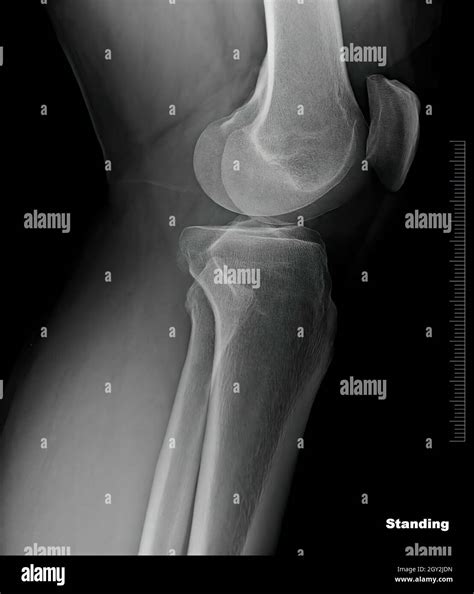

Healthy Knee Xrays

Interpreting Healthy Knee X-rays

Interpreting knee X-rays requires a trained eye. Here are some key features that radiologists look for in Healthy Knee X-rays:

• Bone Structure: The bones of the knee, including the femur, tibia, and patella, should appear smooth and intact without any fractures or deformities.

• Joint Space: The space between the bones should be uniform and not narrowed, which can indicate wear and tear or arthritis.

• Soft Tissue: While X-rays primarily show bone, the soft tissue around the knee should appear normal without any signs of swelling or inflammation.

• Alignment: The knee joint should be properly aligned, with no signs of dislocation or misalignment.

• knee xray side view